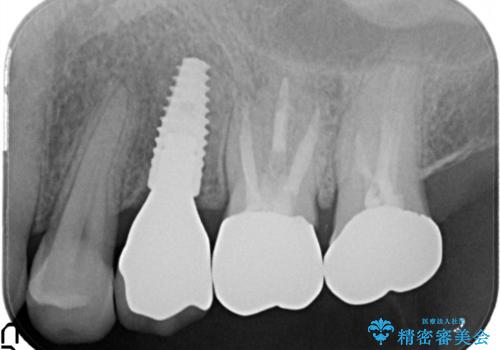

[20代男性] インプラント 失った歯の治療